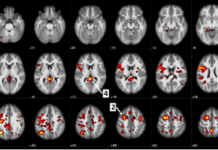

IBM and University of Alberta publish new data on machine learning algorithms to help...

IBM scientists and the University of Alberta in Edmonton, Canada, have published new data in Nature's partner journal, Schizophrenia, demonstrating that AI and machine...